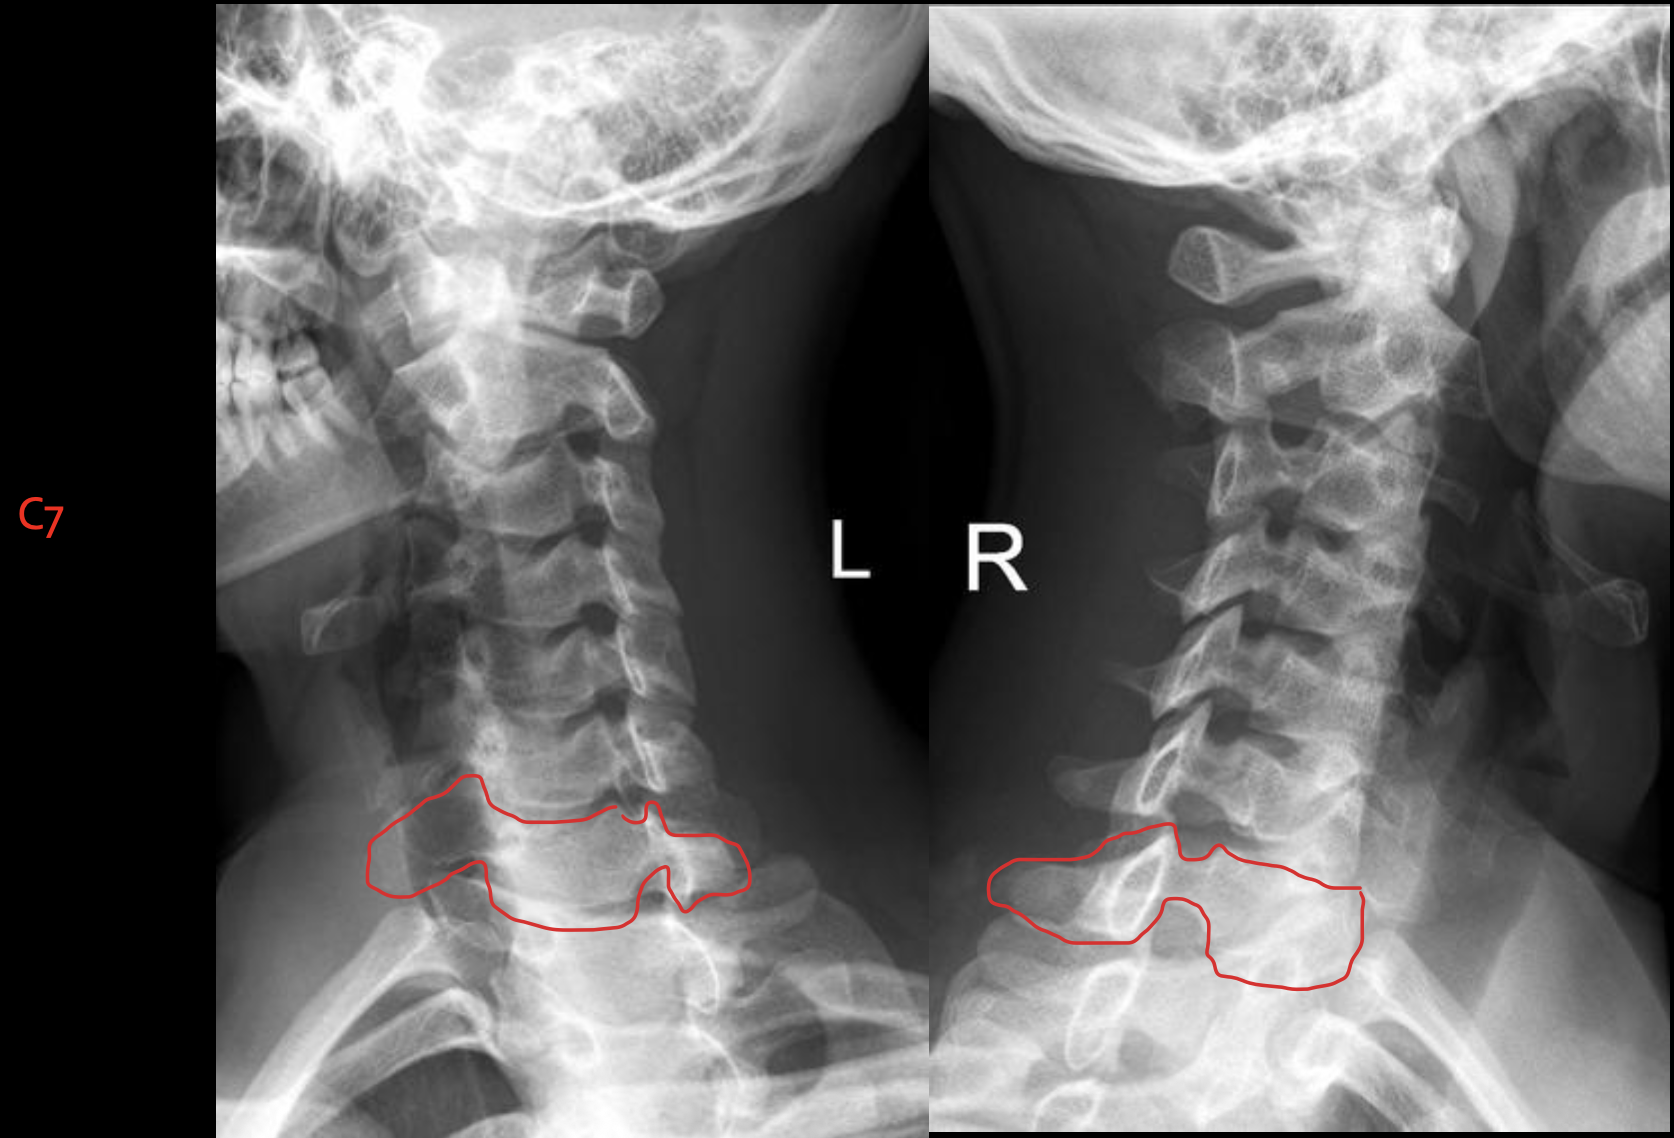

c7